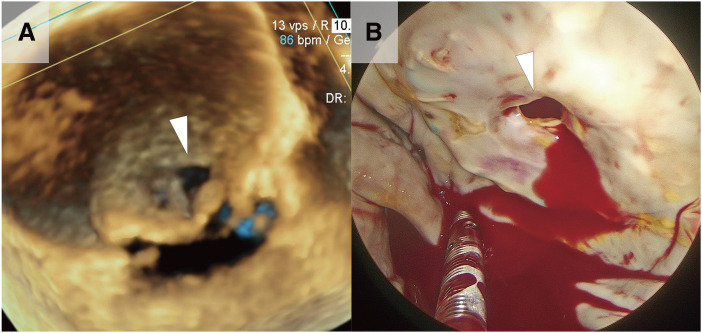

Case presentation: A 76-year-old woman, who had previously undergone mitral valve replacement, was admitted for congestive heart failure. Severe mitral stenosis and severe mitral regurgitation were diagnosed using transthoracic echocardiography. During redo mitral valve replacement, we observed that the prosthetic valve leaflets on the left atrial side were almost entirely covered with pannus tissue, leaving only a central pinhole for blood flow. Macroscopic and microscopic examination of the bioprosthesis revealed accordion-like leaflet deformation on the ventricular side.